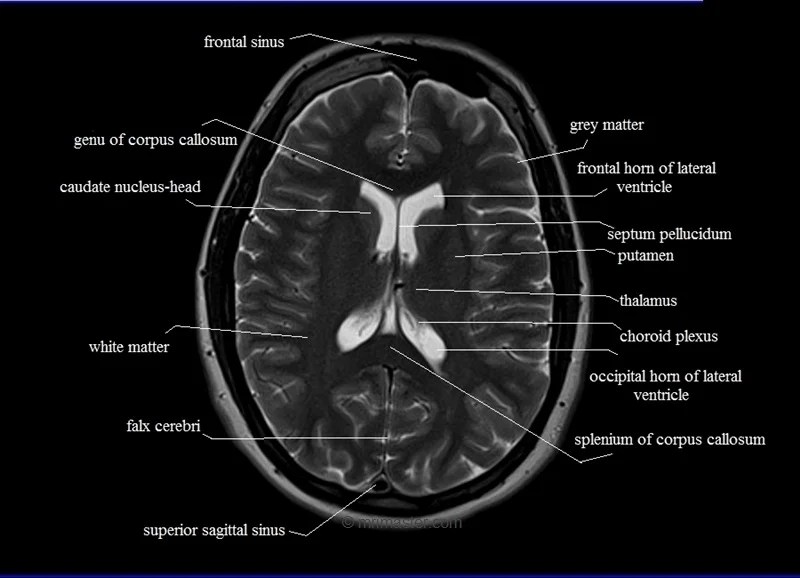

MRI anatomy Free MRI Axial Brain Anatomy Mri Anatomy Axial Note, however, that mcrae’s line (basion. A brain mri is one of the most commonly performed techniques of medical imaging. The anatomy of the brain is studied by means of axial, coronal and sagittal views. Mri axial cross sectional anatomy of brain. The mri sequence used is a 3d gradient. It is the most complete reference of human anatomy available.. Mri Anatomy Axial.